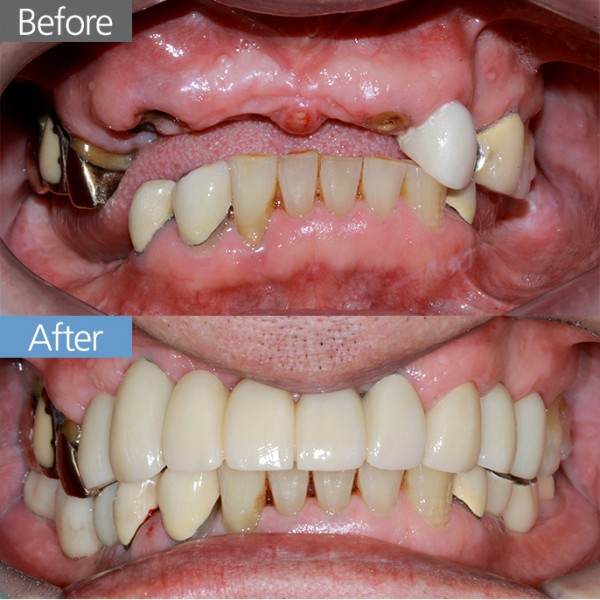

임플란트 70대남 임플란트

70대남 임플란트